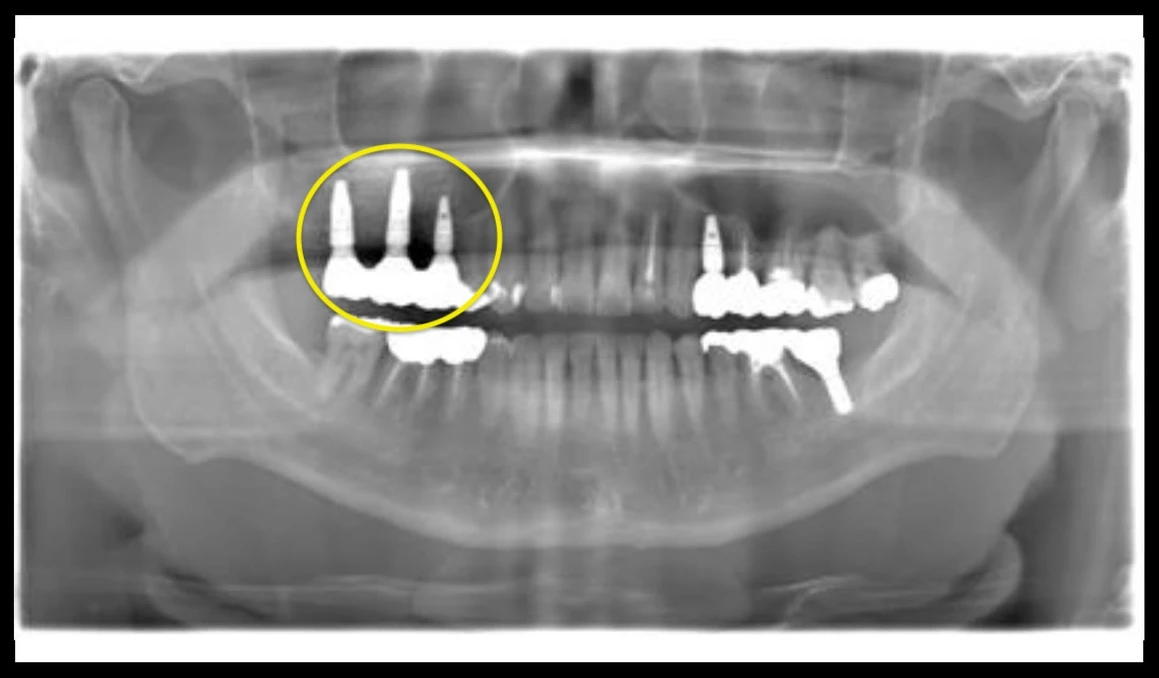

Before

After